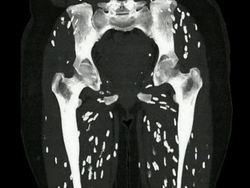

Pasien datang dengan keluhan kelemahan otot dan nyeri. Penyakit ini disebut sistiserkosis otot. Itu disebabkan oleh larva cacing pita di jaringan otot. Foto: Boredpanda